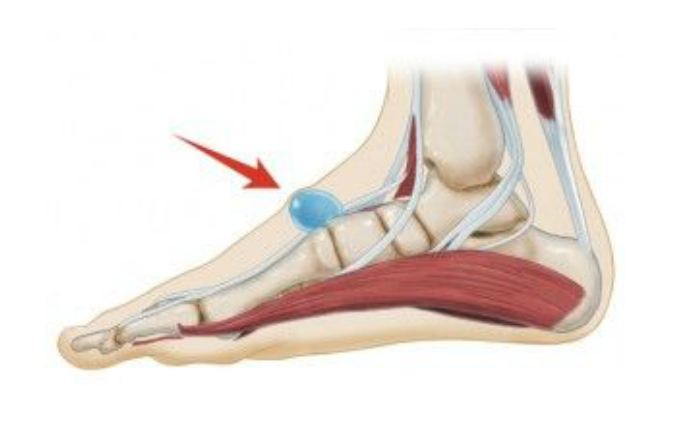

Common Foot & Ankle Disorders

Did you know the foot has 26 bones, 33 joints, 107 ligaments, 19 muscles, and numerous tendons? These parts all work together to allow the foot to move in a variety of ways while balancing your weight and propelling you forward or backward on even or uneven surfaces. It is no wonder that 75 percent of all Americans will experience foot problems at one point or another in their lifetimes.